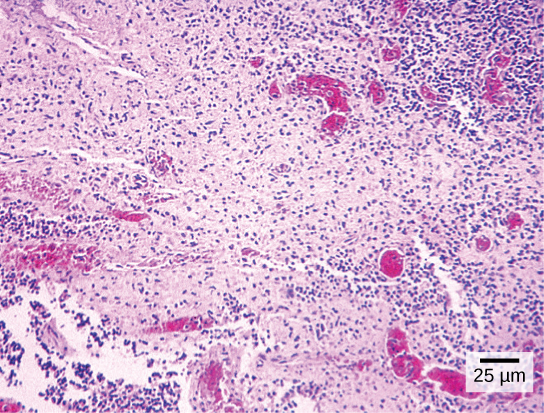

Most student microscopes are classified as light microscopes ([link]a). Visible light both passes through and is bent by the lens system to enable the user to see the specimen. Light microscopes are advantageous for viewing living organisms, but since individual cells are generally transparent, their components are not distinguishable unless they are colored with special stains. Staining, however, usually kills the cells.

Light microscopes commonly used in the undergraduate college laboratory magnify up to approximately 400 times. Two parameters that are important in microscopy are magnification and resolving power. Magnification is the degree of enlargement of an object. Resolving power is the ability of a microscope to allow the eye to distinguish two adjacent structures as separate; the higher the resolution, the closer those two objects can be, and the better the clarity and detail of the image. When oil immersion lenses are used, magnification is usually increased to 1,000 times for the study of smaller cells, like most prokaryotic cells. Because light entering a specimen from below is focused onto the eye of an observer, the specimen can be viewed using light microscopy. For this reason, for light to pass through a specimen, the sample must be thin or translucent.